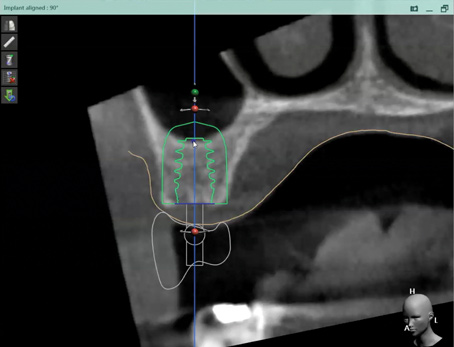

Fig 2. CBCT images show axial (Fig 2) and cross-sectional (Fig 3) views, and 3D reconstruction view (Fig 4) with virtually planned implant Nos. 8 and 9.

Figure 2

Fig 3. CBCT images show axial (Fig 2) and cross-sectional (Fig 3) views, and 3D reconstruction view (Fig 4) with virtually planned implant Nos. 8 and 9.

Figure 3

Fig 4. CBCT images show axial (Fig 2) and cross-sectional (Fig 3) views, and 3D reconstruction view (Fig 4) with virtually planned implant Nos. 8 and 9.

Figure 4